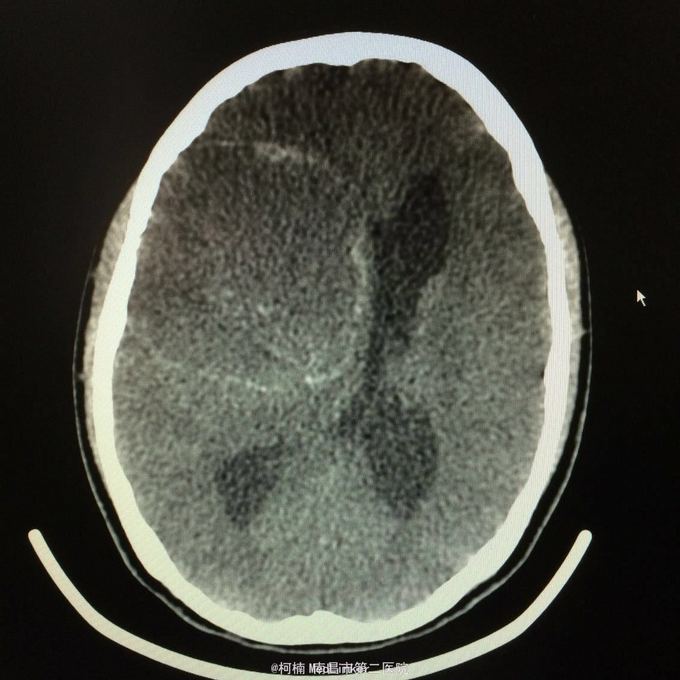

主诉:头痛2年,加重2月 病史:2年前无明显诱因出现头痛,主要为右侧额颞叶胀痛,近两个月来上述症状加重,遂至当地医院行头颅CT提示:右侧额颞叶类圆形异常信号,考虑脑膜瘤合并出血。

神经系统查体阴性 辅助检查:头颅CT提示右侧额颞骨板下肿物伴瘤卒中考虑脑外源性脑膜瘤

右侧额颞脑膜瘤 处理:全麻下行右侧额颞叶占位性病变切除术,术后病理提示:血管型脑膜瘤,WHO1级

随访:病人缓解出院。 讨论:血管型脑膜瘤是一种比较罕见的脑膜瘤类型,脑膜瘤在所有的颅脑部位肿瘤中占到五分之一左右,对于患者的健康会造成一定的影响。而血管型脑膜瘤血管废话藏丰富,对于其治疗会带来很大的困难,就如同血管瘤的手术治疗,术中非常可能会出血,且出血量较大,很难控制。